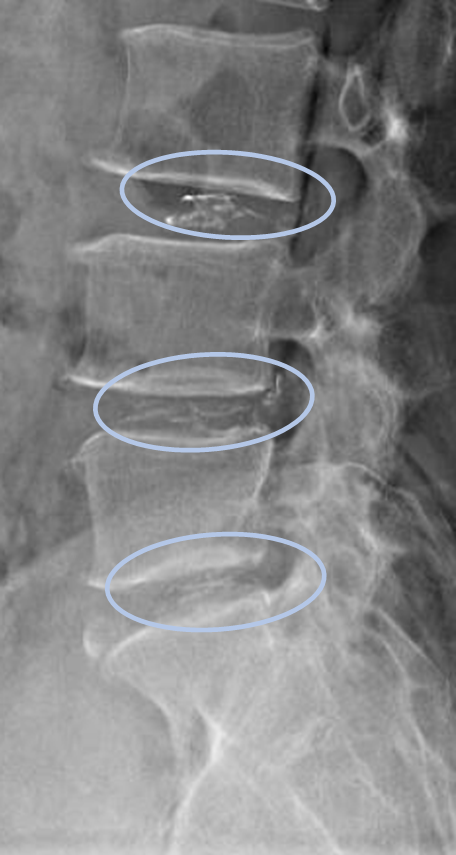

患者様と相談の元、L3/4,4/5,5/sにセルゲル法を施行

DiscoGelを入れた後の画像になります。